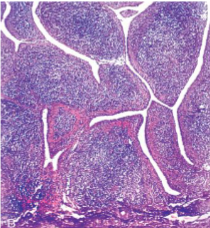

Rheumatoid nodules

Subcutaneous Rheumatoid nodules

Rheumatoid Arthritis

Immune Complex activation of Macrophages

Occur in mostly “pressure areas” such as elbows, ulnar forearm, lumbosacral region, or periarticular; less commonly in visceral organs

Firm, freely moveable, nontender

more frequent in those with severe disease

Histology: palisaded granuloma with central fibrinoid necrosis